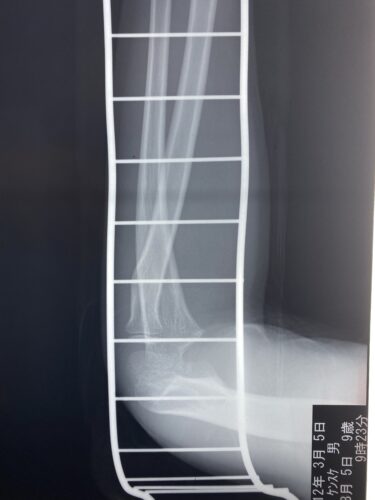

第25回整骨研究会「賜恩」研修会開催

春日部市市民活動センター(前腕骨骨幹部骨折)

第26回整骨研究会「賜恩」研修会開催